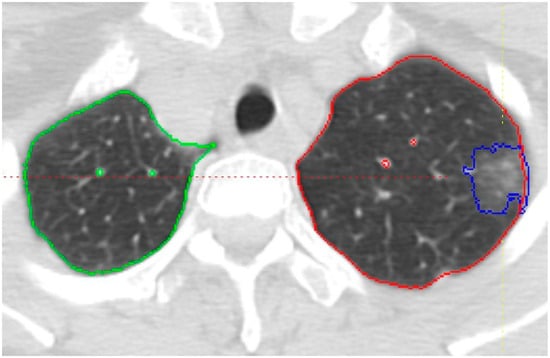

CAD-based texture analysis of nodules for characterization was performed on the same baseline non-contrast CT scan obtained before the biopsy with 1 mm slice thickness at B30f reconstruction. The CT images were imported to an in-house-developed software package, the Quantitative Imaging Workstation (QIWS) developed at UCLA for segmentation and further image analysis. This workstation has a variety of automated and semi-automated CAD and measurement tools. Automatic segmentation function was applied slice-by-slice for each nodule by an operator trained at identifying and segmenting nodules (SJ). Each slice was then carefully reviewed, and manual corrections to the segmentation were made as necessary. Thereafter, a radiologist with 23 years of experience (FA) reviewed the segmentation, performed necessary segmentation adjustments, and finalized the segmentation. A sample of the segmentation is shown in Figure 1. Quantitative features were extracted from the regions of interest using the QIWS software (Version 1), as previously mentioned. These features included shape, intensity histogram statistics, and texture features derived from gray-level co-occurrence matrices (GLCM). Through CAD-based texture analysis, 95 variables were generated, categorized into 11 histogram features, 4 size features, and 80 GLCM texture features (as detailed in the Supplementary Materials). The radiomics calculations followed the Image Biomarker Standardization Initiative (IBSI) guidelines [12].

Figure 1.

Axial CT image showing the segmentation of a part-solid nodule in the left upper lobe, outlined in blue. The right and left lungs are outlined in green and red, respectively. Vessels are segmented separately to distinguish them from the lung parenchyma.